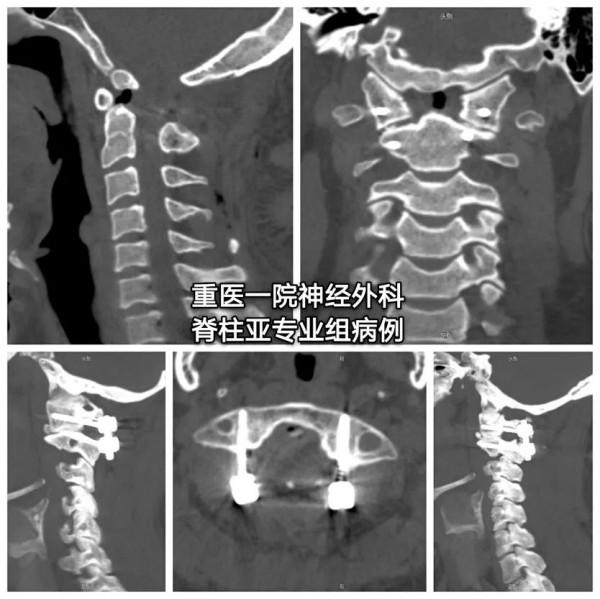

診斷:齒狀突小骨

治療:手術復位固定

還是來看看椎動脈高跨

似乎完全不能置釘?

- 大多數看似不可能置釘的有椎動脈高跨的C2椎弓根,其實都是可以置釘的

- 面對椎動脈高跨,“小心假設,大膽求證”,總能找到合適的釘道。

- 本例選擇靠近C1-2小關節的上關節面和靠近C2峽部內側的位置建立釘道。